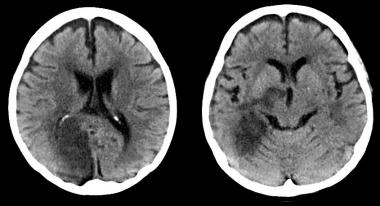

El 7% de los mayores de 65 años operados tuvieron una lesión isquémica cerebral aguda que no produjo síntomas inmediatos, pero que se asoció a mayor deterioro cognitivo en el seguimiento alejado. The Lancet, 21 de septiembre de 2019.